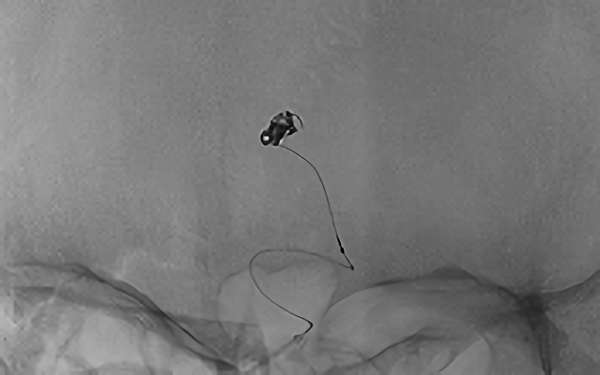

No.1631 手術中